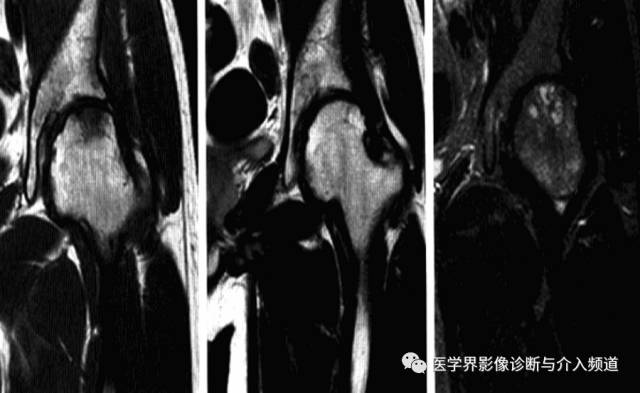

2、MRI:骨头至转子间在T1WI低信号,T2WI及脂肪抑制像呈均匀一致高信号,无局灶性改变,多伴髋关节积液,周围肌肉层次清晰,随访多于6-10个月内恢复正常,无后遗症。